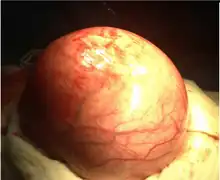

| Uterine fibroids as seen during laparoscopic surgery | |